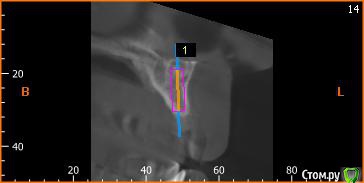

Platon Опубликовано 10 января, 2016 Поделиться Опубликовано 10 января, 2016 Здравствуйте.Помогите с планированием начинающему.Пациентка 38 лет. отсутствует 21. визуально в области 21 провал (фото нет, пока только кт). ходит с акриловой "птичкой"ортопед говорит: ставь, она к эстетике не будет предъявлять претензий))). с чем мне не хочется соглашаться(система ALPHA BIOкак правильно поступить?какие варианты рассматриваю:1. имплантация 3,75 на 11.5 SPI. ,+ временная коронка. Без какой либо пластики.2. костная пластика (мембрана,ксено,) без имплантации, сст, капа на 4 -6мес. потом имплантация + временная коронка3. имплантация, сст , временная коронка С учетом обстановки, прессинга, отсутствия опыта в аугментации, склоняюсь к третьему варианту. заранее спасибо за советы!удачного дня! Ссылка на комментарий

Platon Опубликовано 31 января, 2016 Автор Поделиться Опубликовано 31 января, 2016 Продолжение.не судите строго за фото, первый раз вообще фоткаю операцию)спасибо за советы.По порядку. После того, что мне написали, я решил все -таки уговорить на конусный имплантат (3.7-11.5 ImplantDirect). Также ортопед не хотел делать временную коронку, сказал что сделает каппу, птичку в топку -тоже сделали. Слизистая в области 21 была в рубцах. Исходя из этого всего я решил, коль временной коронки не будет, то сст подсаживать тоже не стану пока,(ортопеда уговаривал сделать временную коронку)))- торк был хороший 35-50н) для того чтобы сст попрактиковаться, но(((.в итоге, анестезия, разрез, сверло пилотное и сверло 2.2, далее расщепление с помощью набора майзенгер с использованием спредеров до нужного диаметра, установил имплантат, торк контролируемый, можно было подобрать любой) в итоге оставил 35. заглушка, совсем немного ксено, мембрана, ушился. ждем. Будет что-то типо каппы которая слегка отдавливает десну,формируя сосочки. не знаю, ни разу такую еще не видел.планирую на этапе раскрытия все-таки сст и временную коронку увидеть.вот. через 4 мес. выложу, что получилось) Если есть советы, критика, всему буду рад, спасибо 3 Ссылка на комментарий

St_Klaus Опубликовано 1 февраля, 2016 Поделиться Опубликовано 1 февраля, 2016 взять 11,5 не заглублять данный имплант, оставить 1,5 мм супракрестально., если позволяет десна, чтобы уменьшить ремоделинг кости. Соглашусь, альфа не предназначена для заглубления, если не ошибаюсь, даже производители не рекомендуют.Если есть советы, критика, всему буду рад, спасибоВсе хорошо, только чуть более небно бы вывел платформу, хотя бы 0,5 мм Ссылка на комментарий